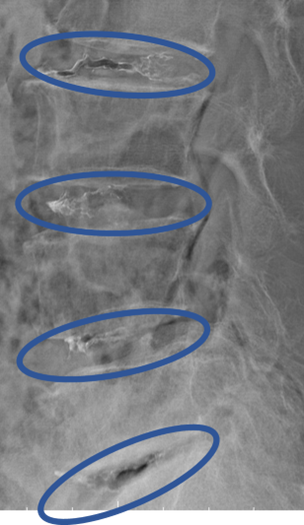

DiscoGelを入れた後の画像になります。

治療は 30分程度で終了

回復室で休憩後、歩いて帰院されました。